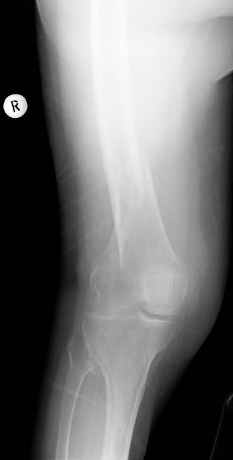

Попробуяю угадать - ретроградный гвоздь? Ну а все-таки - выбор способа фиксации на чем базируется?

>Попробуяю угадать - ретроградный гвоздь?

Вы угадали.

1. остеосинтез должен быть достаточно стабилен,

2. минимальная травматизация мягких тканей,

3. ранняя безболезненная подвижность в соседствующих суставах

4. ранняя аксиальная нагрузка нижней конечности

Это мое мнение. Второй и четвертый пункты при пластинах не выполняются.